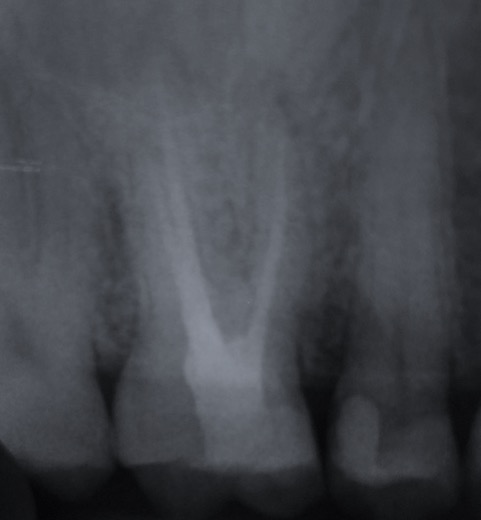

Una corretta terapia canalare con un perfetto sigillo a livello degli apici delle radici è fondamentale. I denti devitalizzati impropriamente possono creare ulteriori problemi che poi andranno a ripercuotersi sulle cure effettuate successivamente come le ricostruzioni e le corone protesiche con conseguente fallimento del piano terapeutico.

Capita spesso di incontrare denti già devitalizzati in maniera impropria che necessitano, seppur asintomatici, di essere ritrattati per evitare che i granulomi infetti visibili radiograficamente si evolvano riassorbendo tutto l’osso sottostante.